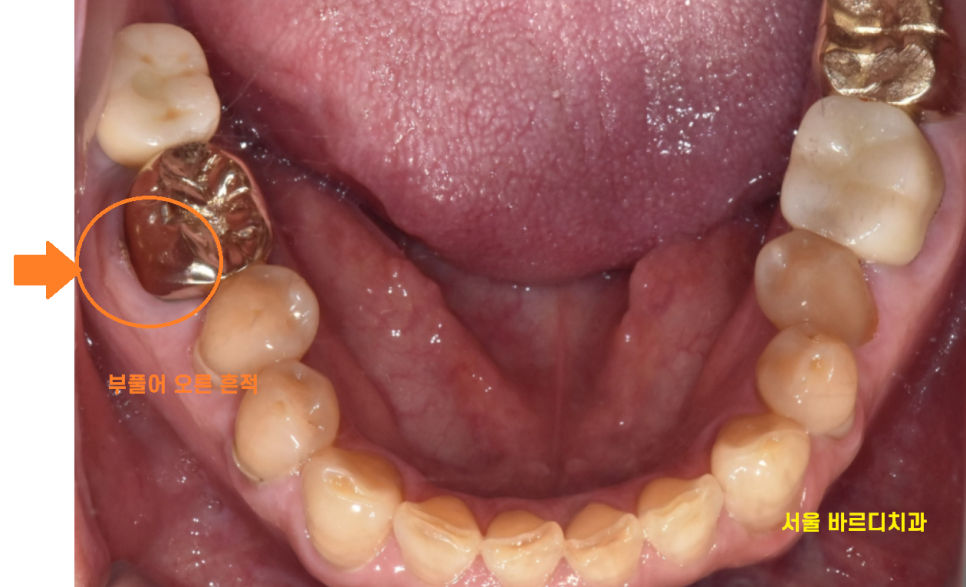

24.06.05

발치 후 2달 정도 지나서

수술을 하였는데

아직 이 뽑은 형태 그대로인게 보이네요~

그만큼 잇몸 풍선처럼 부풀었다 가라앉으면서

뼈를 많이 녹인겁니다